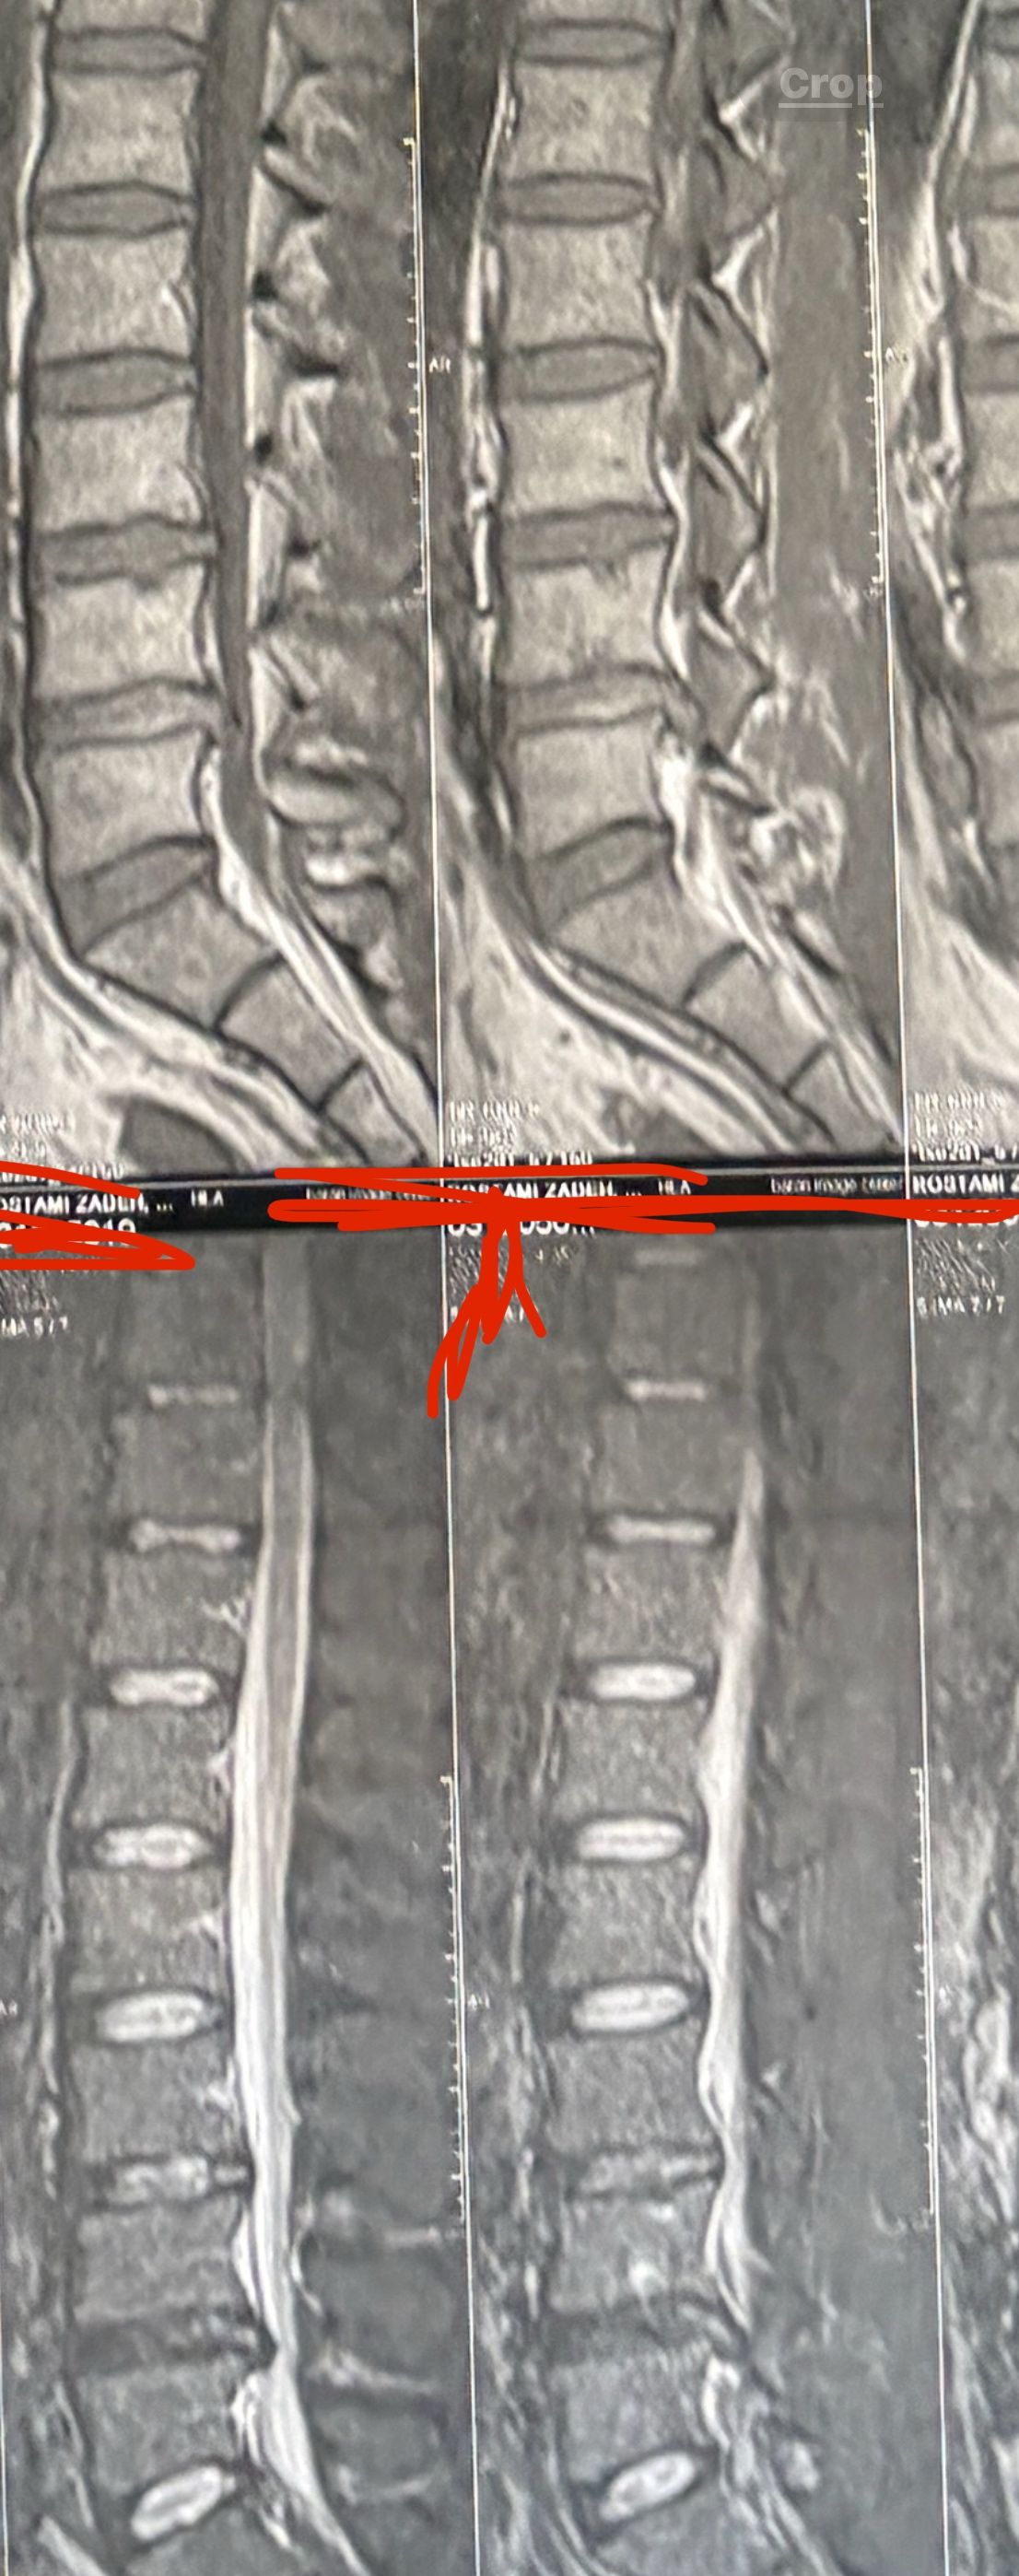

40 yrs old male patient presented to my office who had severe R gluteal pain and radicular pain along R L5-S1 now pain has reduced by 80% in his motor exam had R big toe L5 motor reduced to 4+\5 and R S1 DTR was 0 while L S1DTR was 1+

We did EMG/NCV which showed Mod- sever R L5 S1 irritation without any active axonal loss

I had to decide to refer him for surgery or not patient didn’t have any treatment meanwhile

I ordered new L/S mri

I posted his new mri and old mr

Which was 20 days ago and have posted all below

The first 12 mris had been done 20 days ago

After those first 12 MRIs i have posted new MRIs which were done yesterday

After seeing his new mri and emg/ncv and getting sure his neurological deficit is not active and progressing i told patient he doesn’t need surgery at this time and released him with some advices and exercises

Keep in mind when patient is 80-90 percent pain free and stable i would never give treatment to them just give exercises and follow up their condition